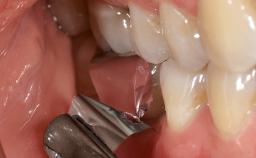

Surgical Management of Peri-Implantitis: Removal of Implant Due to Recurrent Infection Using an Implant-Retrieval Tool

Despite anti-infective surgical treatment, some patients may experience recurrent infection and progressive bone loss requiring additional treatment. This case describes a conservative approach using an implant retrieval tool without the need for excessive bone removal or use of a trephine.